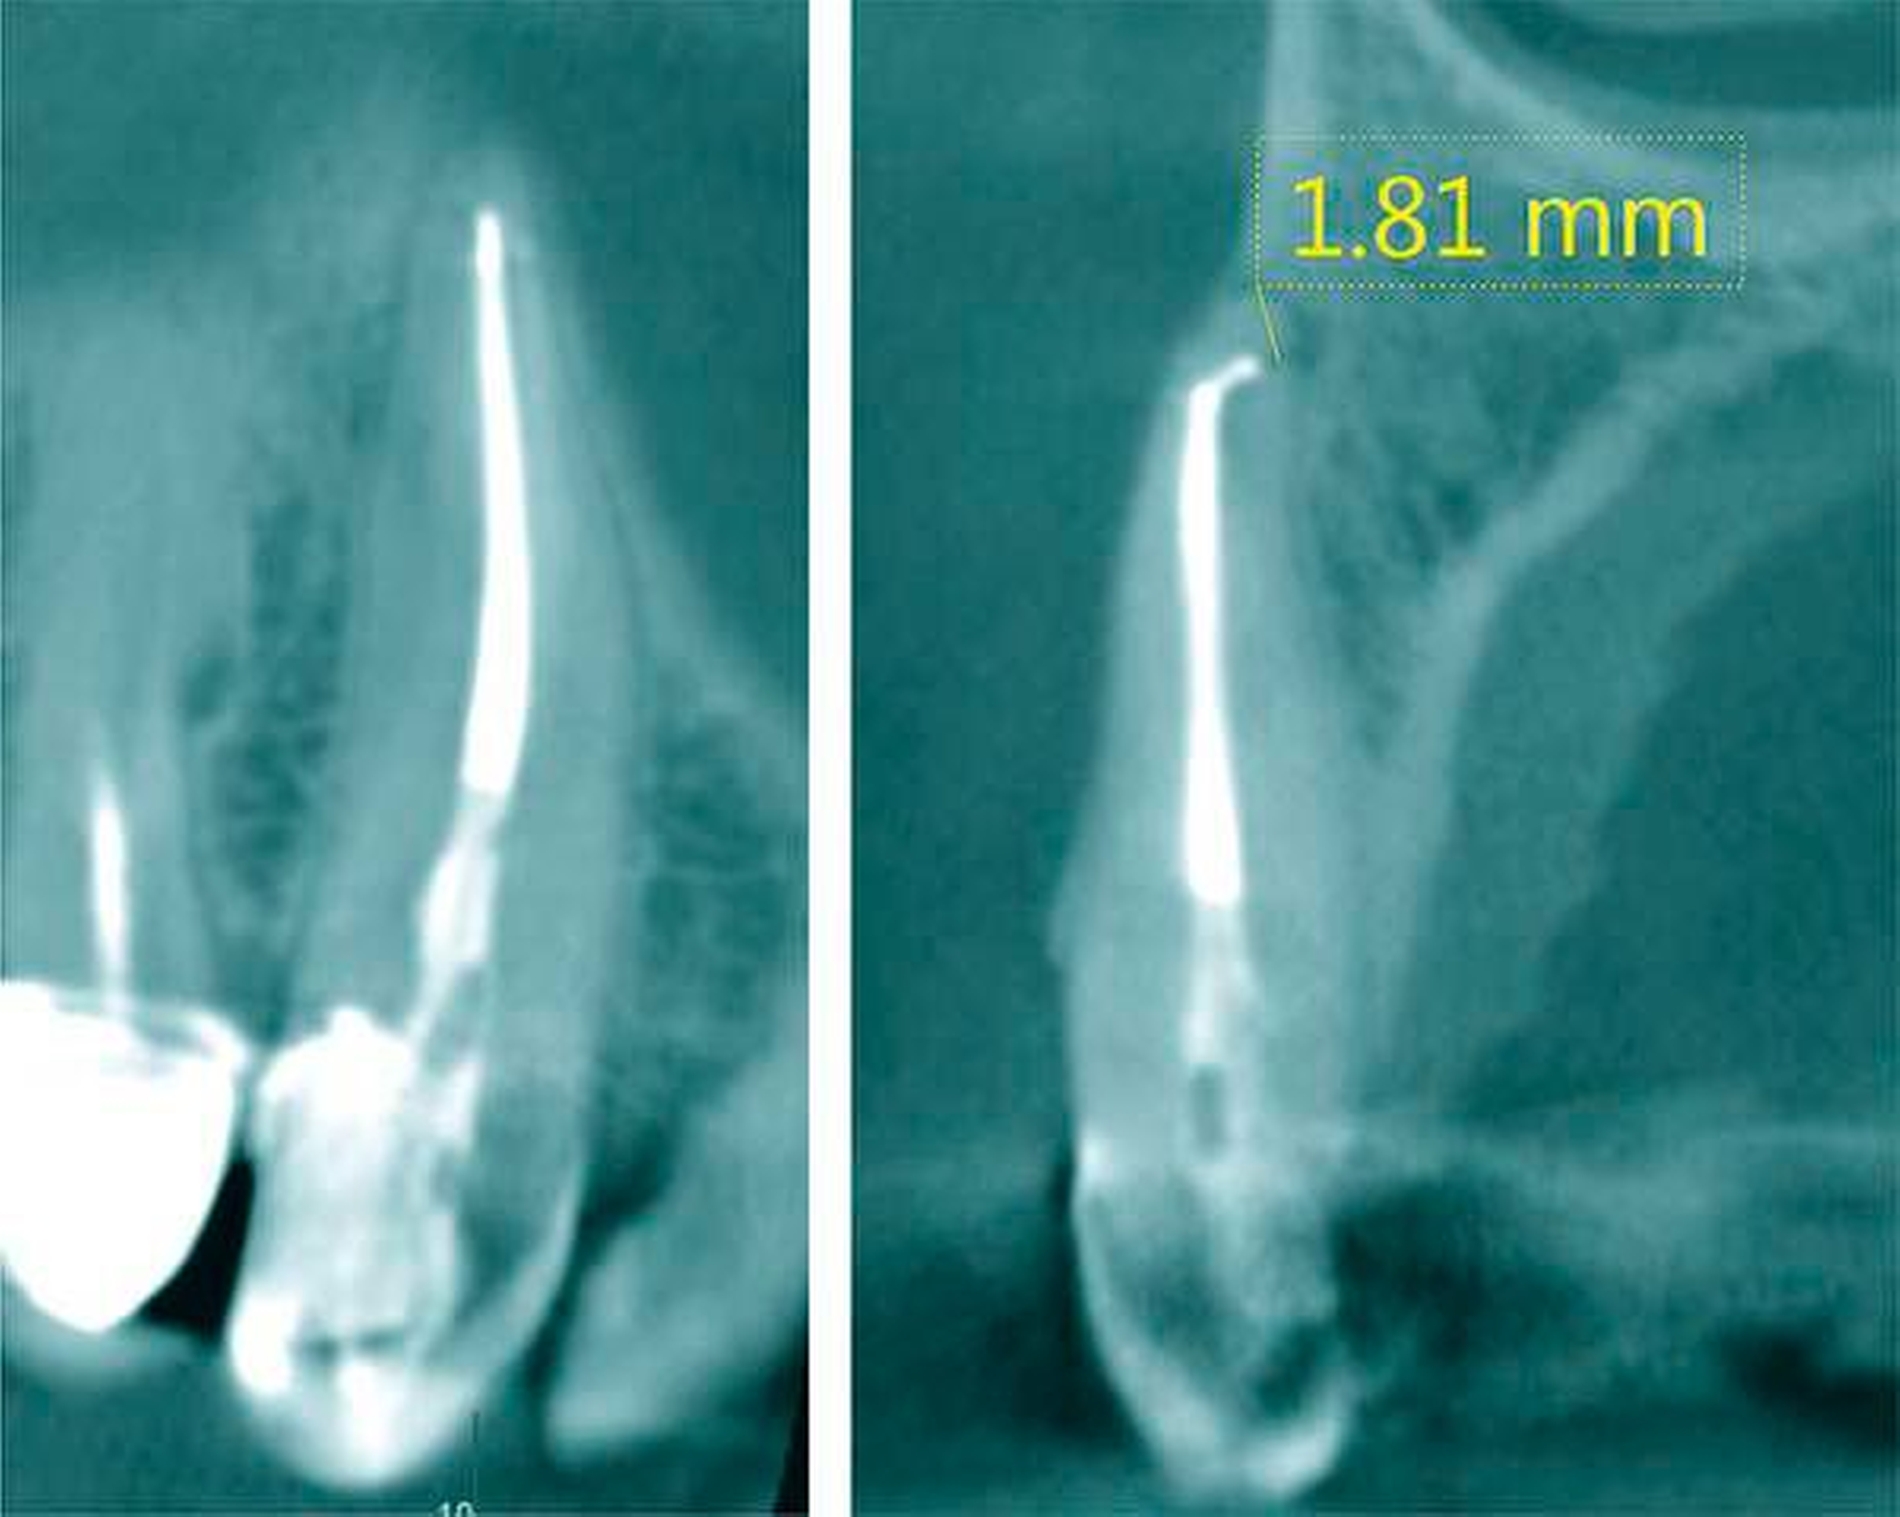

Apikal kann die Wurzel einen geraden Verlauf einnehmen, der Wurzelkanal aber innerhalb der geraden Wurzel stark gekrümmt verlaufen. Insbesondere auf rechtwinkligen intraoralen Röntgenaufnahmen kann die apikale Krümmung eines Wurzelkanals projektionsbedingt nicht exakt abgebildet werden.

Von klinischer Bedeutung sind bei seitlichen Schneidezähnen (und Eckzähnen) mehrere anatomische Besonderheiten. So können die nach distal gerichteten apikalen Krümmungen eine vollständige Erweiterung und Desinfektion erschweren. Die apikale Begradigung und Verlagerung des apikalen Foramens mit iatrogener Vergrößerung, die Verblockung mit Debris oder die Fraktur von Wurzelkanalinstrumenten sind keine seltenen Komplikationen – sie können das Ergebnis der Wurzelkanalbehandlung negativ beeinflussen (Abbildung 12).

Das apikale Foramen endet in nur 70 Prozent in Verlängerung des Wurzelkanals an der Wurzelspitze. Die laterale Lage des Foramen apicale kann auf zweidimensionalen Röntgenaufnahmen den Eindruck einer zu kurzen Arbeitslänge vermuten lassen (Abbildung 19).